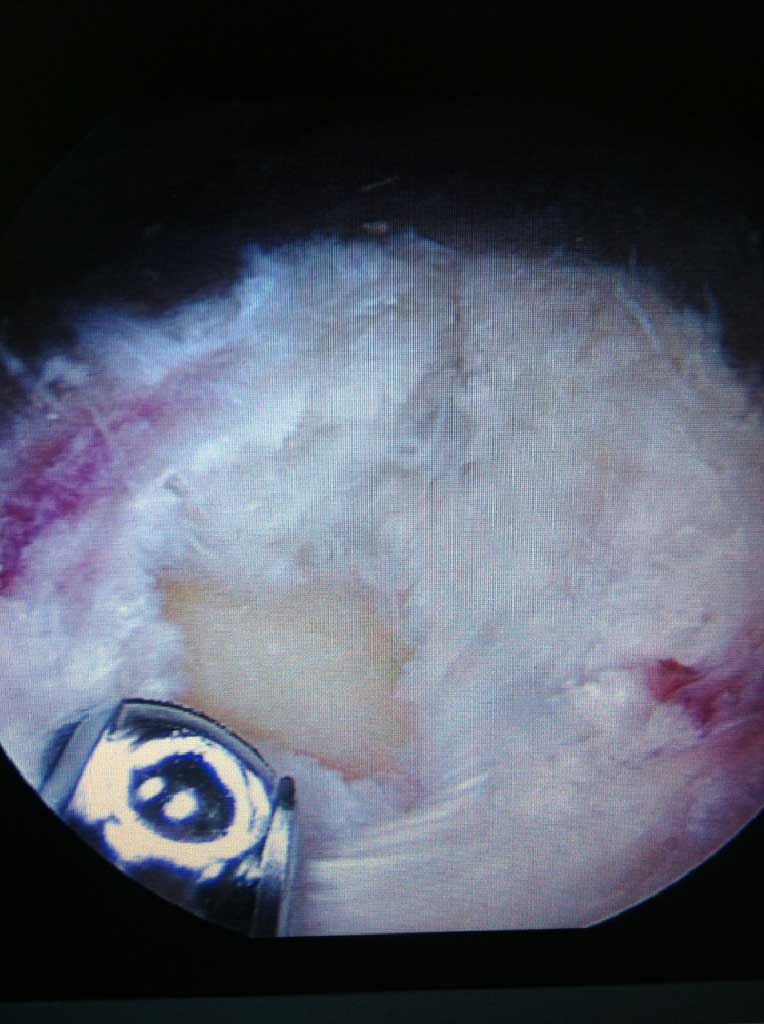

Wird die Indikation zur Sehnennaht / Rekonstruktion der gerissenen Sehnen gestellt, so wird die Operation in unseren Händen ausschließlich arthroskopisch (Schlüsselloch Operation) durch 3 - 6 kleinen Stichinzisionen (3-4mm) durchgeführt. Dieses operative Verfahren ist maximal zu den schulterumgebenden  Weichteilen schonend.

Je nach Alter, Verletzungsmuster, Anzahl der Luxationsereingnisse und weiteren Faktoren, wird eine schulterstabilisierende Operation indiziert und empfohlen. Diese führen wir ebenfalls ausschliesslich arthroskopisch

(Schüsselloch Operation) durch. Innerhalb von 15 - 30 min wird dabei der knorpelige Ring (s.g. Labrum) auf den knöchernen Pfannenrand mit speziellen Anker und Fäden wieder zurück befestigt.